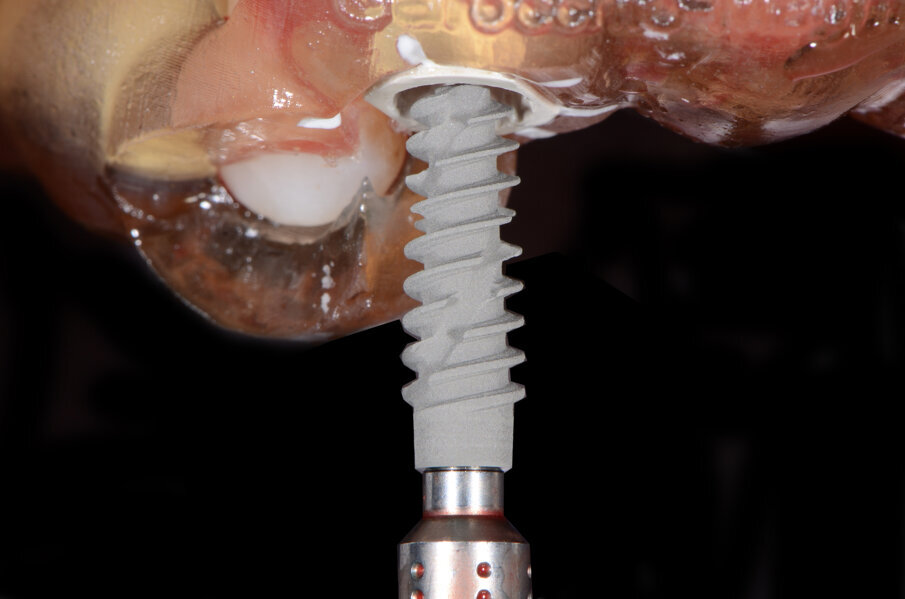

Il nostro obiettivo è quello di riuscire a dare alla paziente un provvisorio immediato nell’arco di due ore. Questo diventa possibile perché abbiamo utilizzato un flusso digitale fin dall’inizio. In laboratorio vengono realizzate la dima chirurgica (Figg. 16, 17), la dima protesica (Fig. 18) e anche il provvisorio (Figg. 19-21) che contiene delle alette di riposizionamento. Il tutto gestito con modelli digitali sui quali saremo in grado di funzionalizzare il provvisorio post-chirurgico (tecnica DIL). In un caso come questo se utilizziamo un flusso digitale possiamo evitare subito dopo la chirurgia di rilevare un’impronta degli impianti inseriti. Infatti, utilizziamo una dima chirurgica che ci faciliterà le fasi di intervento. La dima ci consentirà di non fare lembi e nessuna incisione di rilascio (Fig. 22), dopo aver inserito gli impianti (BLX Straumann) (Figg. 23-31) e aver controllato il loro alloggiamento, inseriamo sugli stessi dei transfert da impronta (Fig. 32).

Fig. 26 - Impianto BLX Straumann.

Fig. 27 - Posizionamento impianto 1.2.

Fig. 28 - Alloggiamento finale.

Fig. 29 - Posizionamento impianto 2.2.

Fig. 30 - Alloggiamento finale.

Il piano di trattamento prevede l’estrazione degli elementi dentali, l’inserimento di due impianti e la realizzazione di una protesi fissa di quattro elementi. Il problema da gestire è quello della fase provvisoria. Non è ipotizzabile una protesi mobile e quindi programmiamo di inserire subito dopo l’intervento un provvisorio immediato. Questo ci consente di condizionare da subito i tessuti periimplantari e anche le zone dei ponti. Si rileva un’impronta digitale (Figg. 5, 6), e la programmazione degli impianti viene effettuata con un software di chirurgia guidata (Fig. 7) e la posizione degli impianti nello spazio biologico e nello spazio protesico viene fatta sulla base di una ceratura diagnostica (Figg. 8, 9). Inseriamo gli impianti virtuali nell’osso disponibile (Figg. 10-13) e in relazione all’aspetto protesico correggiamo l’asse di inclinazione degli impianti con componenti secondarie angolate a 17° (Figg. 14, 15). Questo ci consentirà di realizzare una protesi avvitata con i fori situati nella zona palatale.